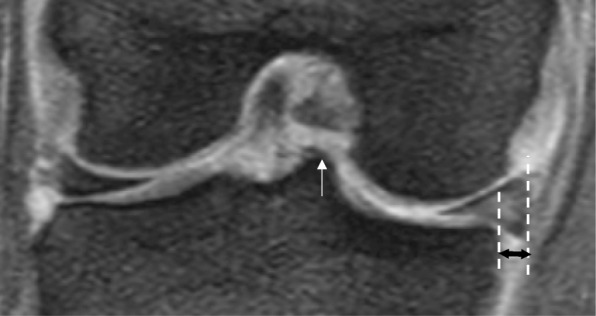

Fig. 3.

Magnetic resonance image-based measurement of medial meniscus extrusion (MME). Measurement of MME is performed using a bony landmark method. On the coronal plane, the medial tibial eminence (white arrow) is used to measure the horizontal distance between the most medial aspect of the tibia and the most medial aspect of the meniscus (black double-headed arrow)